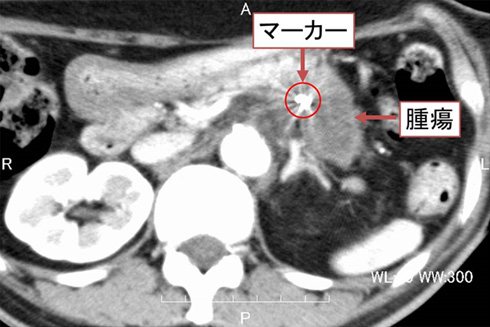

粒子線治療の標的となる腫瘍の多くは、呼吸や心拍動、消化管の動き、消化管内の残渣や便によって不規則的に動きます。あらかじめ「照射用マーカー」を腫瘍近傍に留置しておくことによって、それらの動きや腫瘍の形態の変化をX線透視画像によって検知することができるようになり、粒子線ビームを正確に腫瘍に当てることができます。

マーカーには金や白金を形成した微小の金属を用います。臓器や目的によって様々な専用のマーカーが作られており、留置の方法によっても使い分けます。